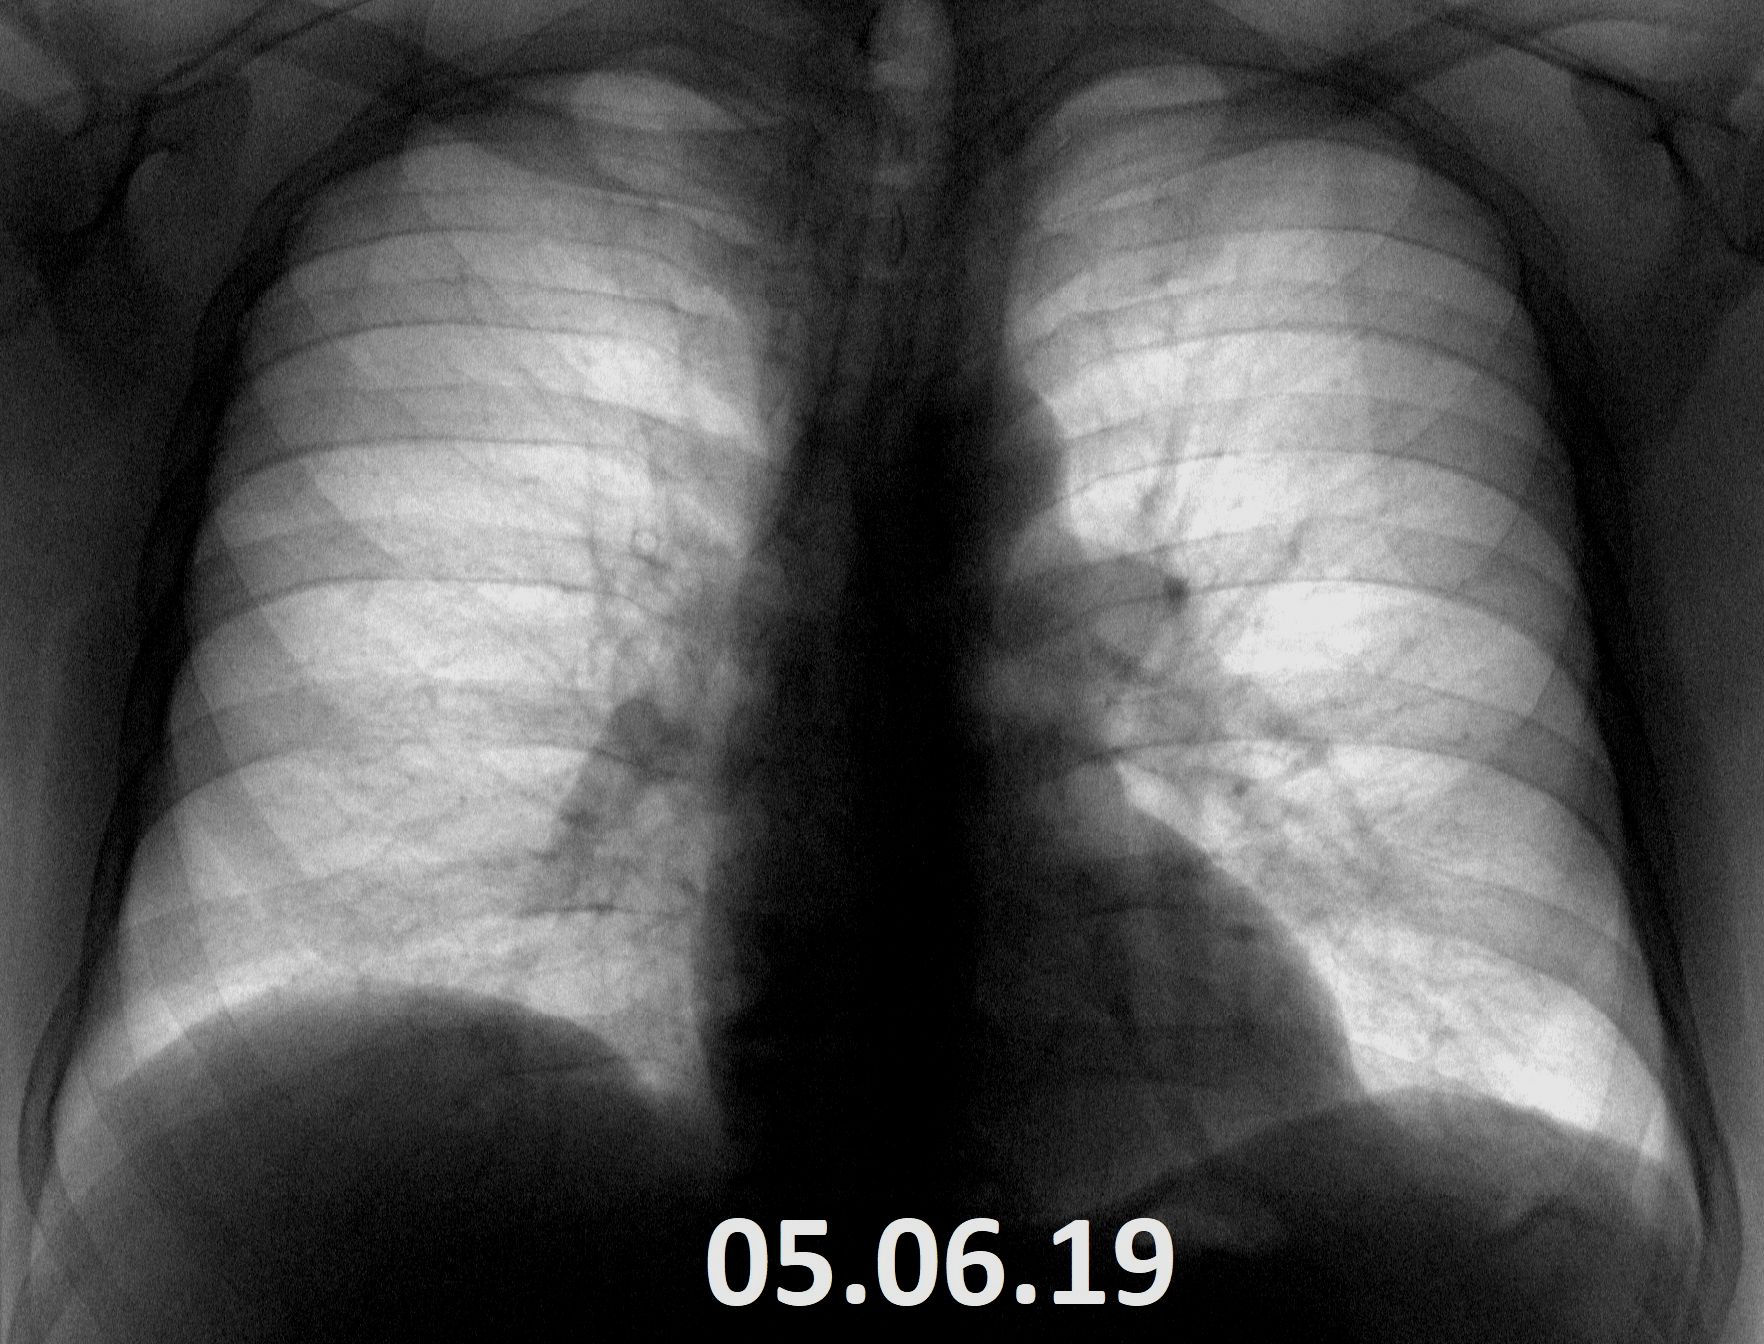

Вчера на 2-й смене  у моего коллеги было продолжение этого случая. Пациент задыхался, лаборанты перепугались. Не дай бог будет летальный исход. Выставляю снимки в хроникальном порядке + архив. Может прошлый раз чего не досмотрел?

Я бы мужу 26.01.2021 норму поставил. Опять же глазами на негатоскоп и глазами на экран телефона вещи разные

А ВЫ сомневались. Даже задним числом к 26.01.21г не придрался. При вырусных на рентгене от нормы до патологии порой достаточно часов.